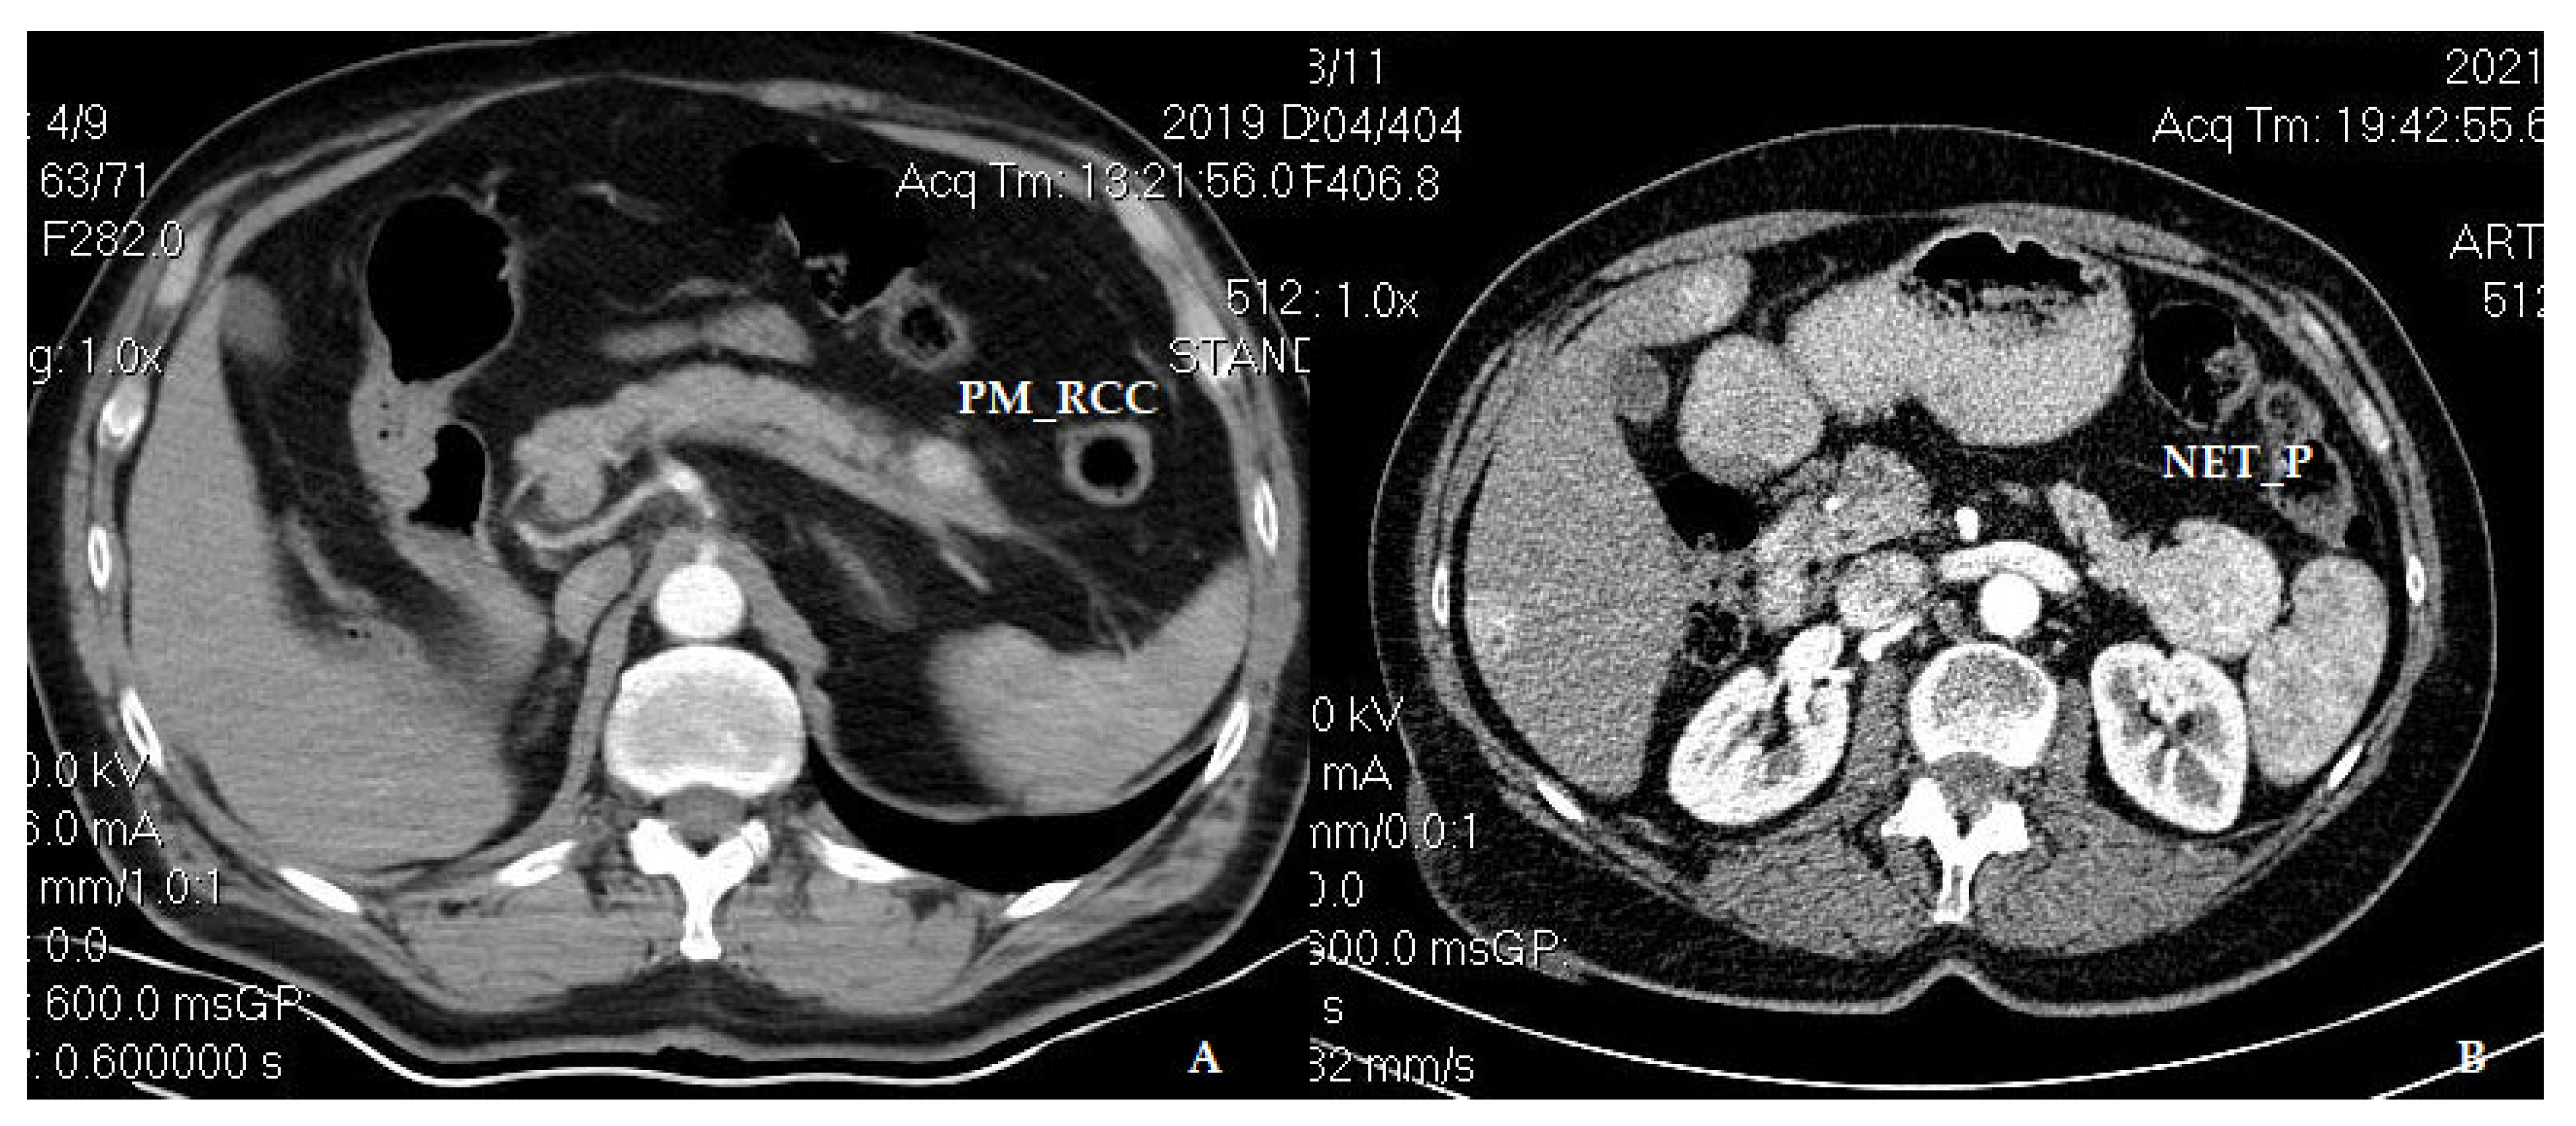

- Krisboi, I.; Breazu, C.; Pop, M.; Iancu, C.; Bartoş, A. Multiple Pancreatic Metastasis of Clear Renal Cell Carcinoma Associated with Neuroendocrine Tumor. Chirurgia 2023, 118, 317. [Google Scholar] [CrossRef] [PubMed]